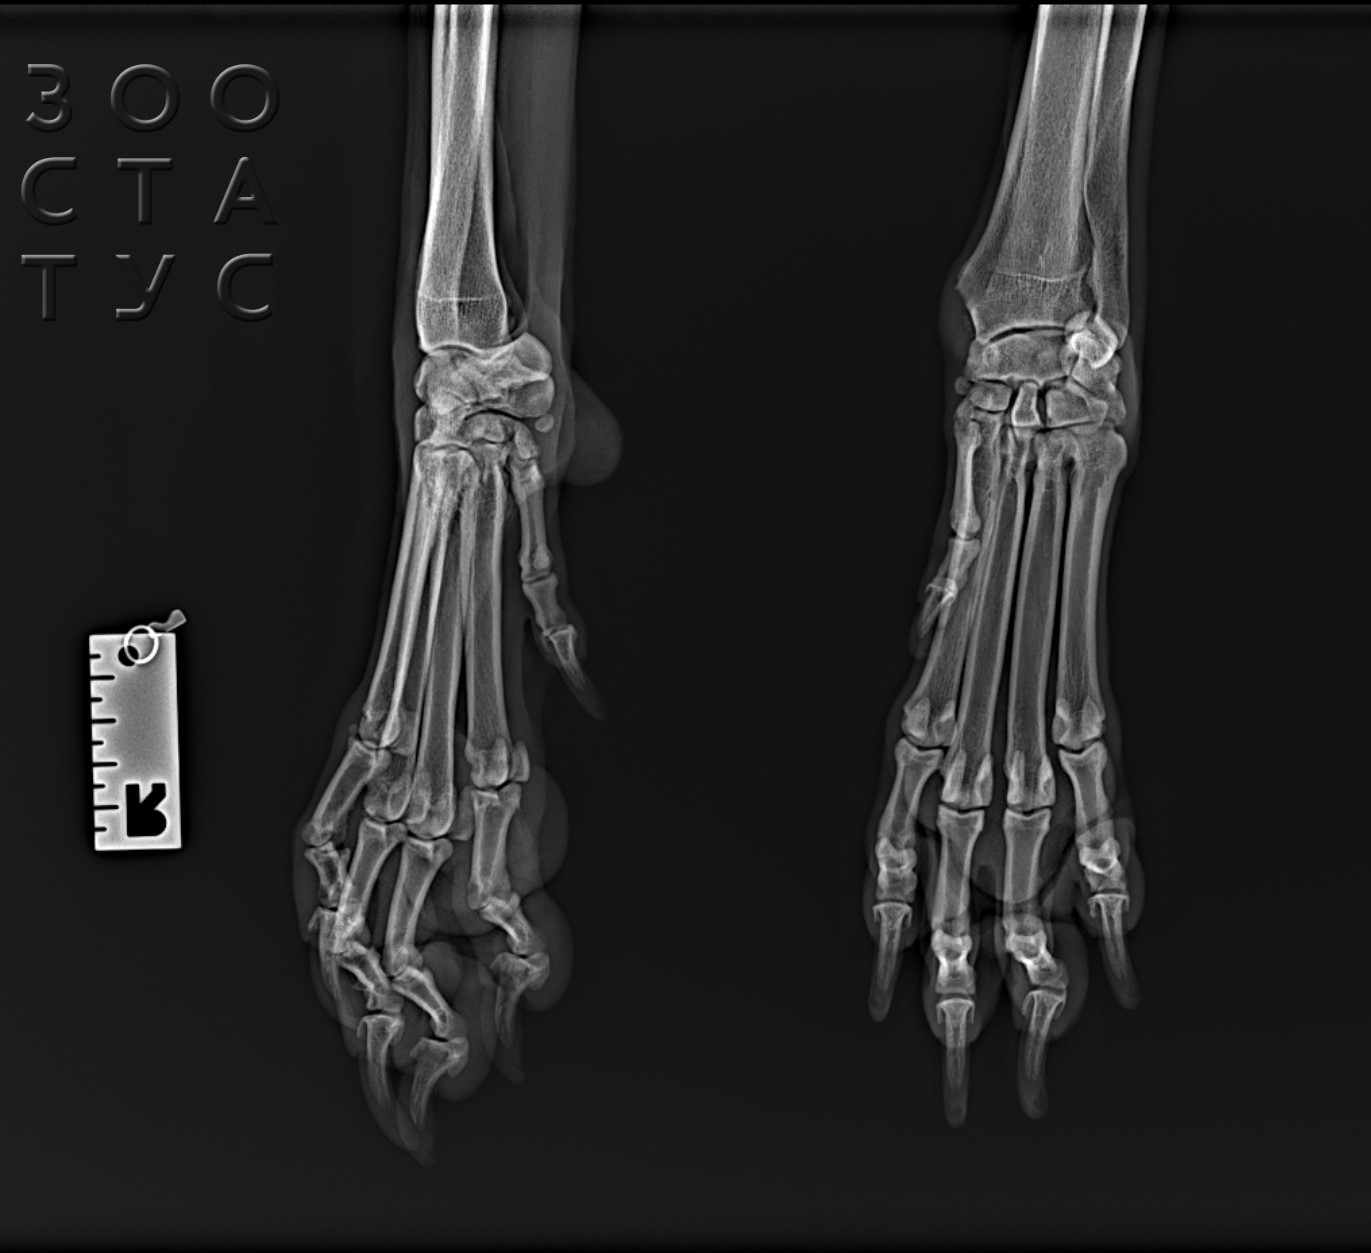

Рентгенографическое исследование (рентген, рентгенография) - один из наиболее востребованных методов диагностики кошек. Один из самых древних неинвазивных (не требующих проникновения под кожный покров) методов, рентген остается актуальным, эффективным и доступным способом диагностировать множество патологий. Рентген на первом месте в качестве способа диагноза травм костной ткани и суставов, очень важен при диагностике после автотравм или падений с высоты, а дополнительные методы, в том числе использование рентгена с контрастом, значительно расширяют сферу его применения.

- после автотравм, падения с высоты - рентген позволяет не только выявить переломы конечностей у кошки, но и обследовать грудную клетку, вовремя выявив жизнеугрожающие травмы;

- рентген лап обязательно нужен при любых других травмах, проблемах с опорно-двигательным аппаратом, хромотой, вялости (кошки хорошо могут скрывать болезненные ощущения после ушибов или растяжений, просто начинают меньше двигаться);

Практически всегда для ортопедического обследования (травмы, хромота) седация необходима, так как иначе невозможно будет расположить сустав в нужной проекции - животное будет дергаться, выворачиваться, и данные исследования могут быть значительно искажены. Также рентген для кошек проводится под седацией для агрессивных, сильно напуганных кошек, с которыми владелец не может справиться.